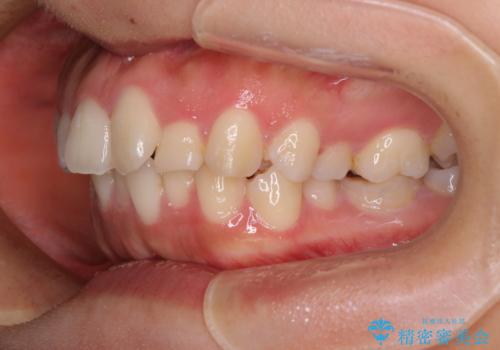

- 咬み合わせと口元の突出感を気にして来院された患者様です。

上顎に対して、下顎が後方にある咬み合わせであるため、上顎左右小臼歯のみの抜歯か、下顎左右小臼歯も抜歯とするのか悩むところでした。

まずは上顎のみ抜歯を行って矯正治療を進め、下顎小臼歯も抜歯が必要となれば速やかに抜歯することとしました。